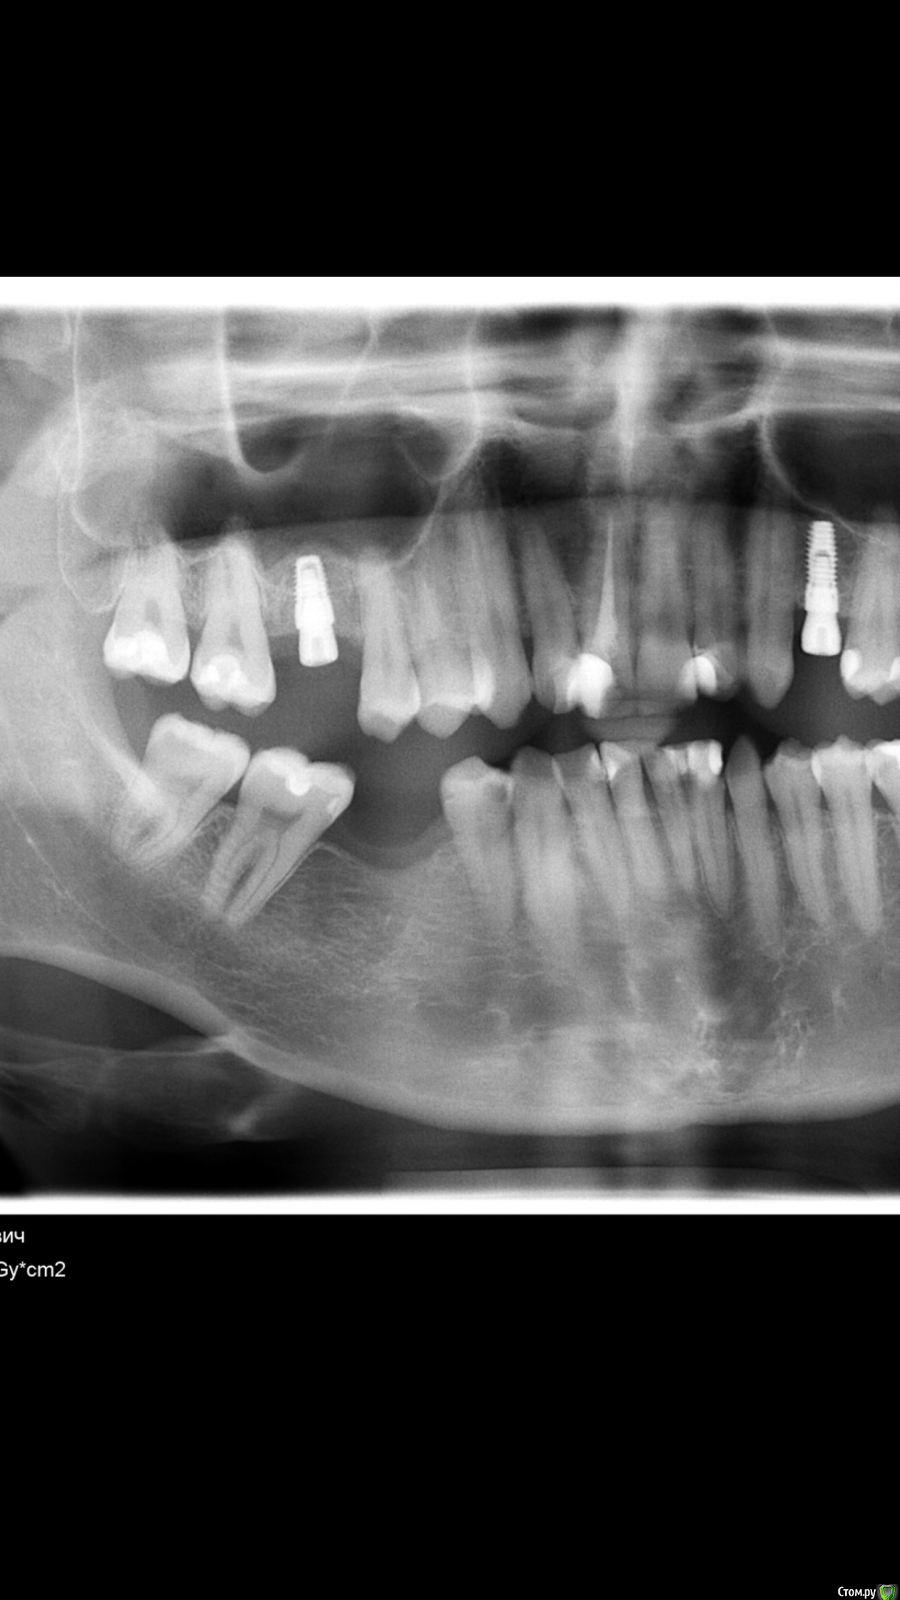

Дмитрий М Опубликовано 7 июня, 2020 Поделиться Опубликовано 7 июня, 2020 Второй фэйл. Тоже свой косяк. Сделал ОСЛ, имплант, получил хороший торк и решил фдм закрутить Судя по снимку, пациент просто накусил на формик. Ссылка на комментарий

ilnurik Опубликовано 7 июня, 2020 Автор Поделиться Опубликовано 7 июня, 2020 Судя по снимку, пациент просто накусил на формик. Да. Я тоже так думаю Ссылка на комментарий